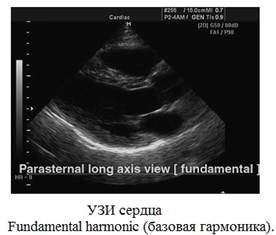

Pulse Inversion Harmonic или тканевая инверсная гармоника - технология выделения гармонической составляющей колебаний внутренних органов, вызванных прохождением сквозь тело базового и инверсного ультразвуковых импульсов. Полезным считается сигнал, полученный в результате сложения базовой и инверсной составляющих отраженного сигнала. Как правило, инверсная гармоника (по сравнению с прямой гармоникой) обеспечивает лучшее качество, потому что оба сигнала (базовый и инверсный) проходят сквозь тело и при сложении автоматически фильтруются шумы. Наиболее целесообразно применение технологии инверсной гармоники при исследовании движущихся тканей (сосуды, сердце) и трудновизуализируемых тканей (с похожей аккустической плотностью), таких как опухоли.